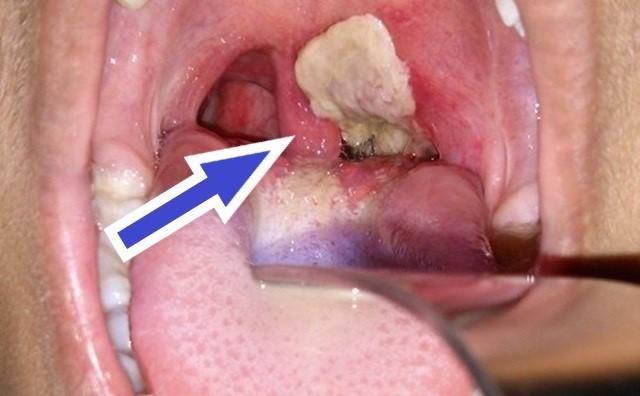

Khi mắc bệnh bạch hầu, bên trong cổ họng và amidan người bệnh thường xuất hiện màng giả có màu trắng ngà, lớp màu trắng mọc thành từng mảng lớn. Ảnh minh họa

Khi bệnh trở nặng, bên trong cổ họng và amidan người bệnh xuất hiện màng giả có màu trắng ngà. Lớp màu trắng mọc thành từng mảng lớn, dai và dính, khi bóc màng ra gây chảy máu, khiến bệnh nhân bị tắc nghẽn đường hô hấp và ho khan.